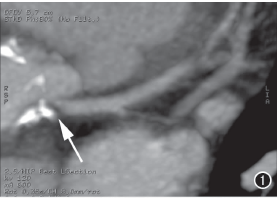

图1 左主干开口部可见钙化,管腔局限性重度狭窄(箭)。